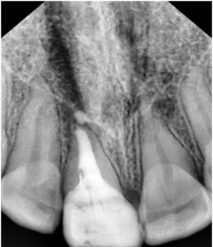

Realizamos radiografía panorámica y periapical de la zona, donde podemos observar que le queda un resto radicular, el cual presenta una gran infección periapical, parece llevar intraconducto un material intraconducto y una obturación provisional sobre el mismo. Esta obturación provisional está completamente suelta y filtrada.

Procedemos a la realización del tratamiento conservador. Empezando por la apicoformación, endodoncia y restauración del diente. A continuación podemos ver una sucesión de radiografías con la evolución del tratamiento del paciente y la intervención realizada.